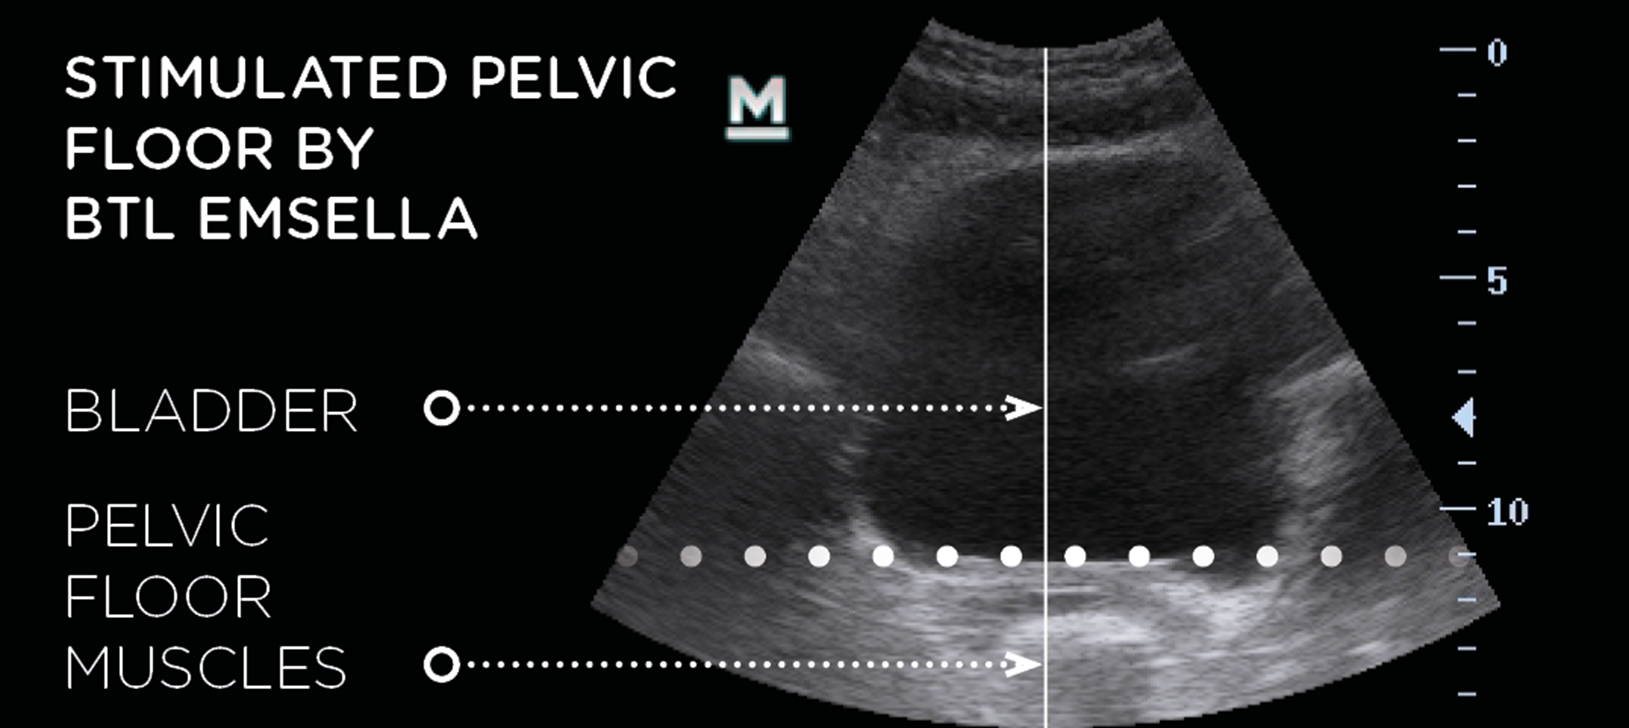

- How It Works: Emsella delivers focused electromagnetic energy to the pelvic floor muscles, causing thousands of supramaximal contractions in a single session. These contractions are much stronger than what can be achieved through regular Kegel exercises.

- Result: Over time, this leads to improved muscle tone and strength, which supports the bladder, uterus, and rectum, improving overall pelvic function.

- Before

- After